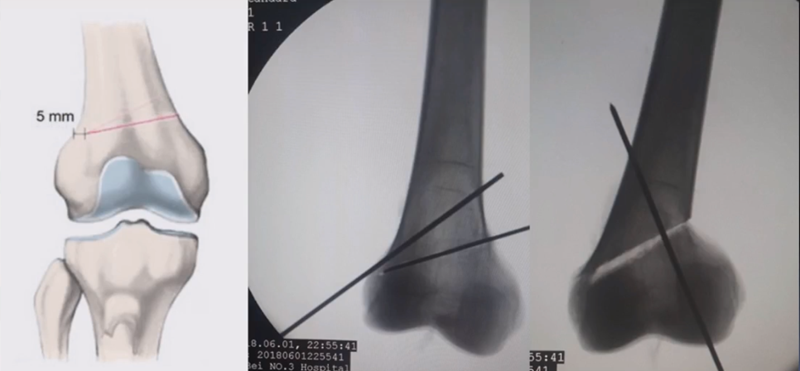

合页点的选择与HTO一样,通常需要尽可能接近畸形部位,既要有很好的骨质结构,还要有坚韧的软组织覆盖,以保证稳定性和术后有良好的血运。合页宽度不宜太长,通常保留在5mm。

截骨线入点同样也可以采用两种方法选择。一种为钢板标记法,即使用tomfix钢板远近端的无孔区作为截骨入点。

另一种为解剖标记法,在切开显露后可以看到一处恒定血管,即内侧上横动脉,在此附近做截骨即可。如做外侧闭合楔时,同样在外侧也可以看到一处恒定血管,为外侧横动脉。

合页点和截骨线已确定好,按照术前计划打入导针,测量截骨深度。

注意,目前临床推荐的DFO要求最好能做双平面截骨,即还要有一条上行截骨线,上行截骨线与水平截骨线夹角大概为95° 左右。这种截骨方式一方面可以增加稳定性,同时也可以减少对上方髌股关节的干扰。

上行截骨时,要保持肢体旋转中立位,前方要有骨撬保护,由内向外完全截开,上行截骨线不存在合页。

水平截骨时,同样放肢体中立位,后侧放一把骨撬保护后方重要结构。